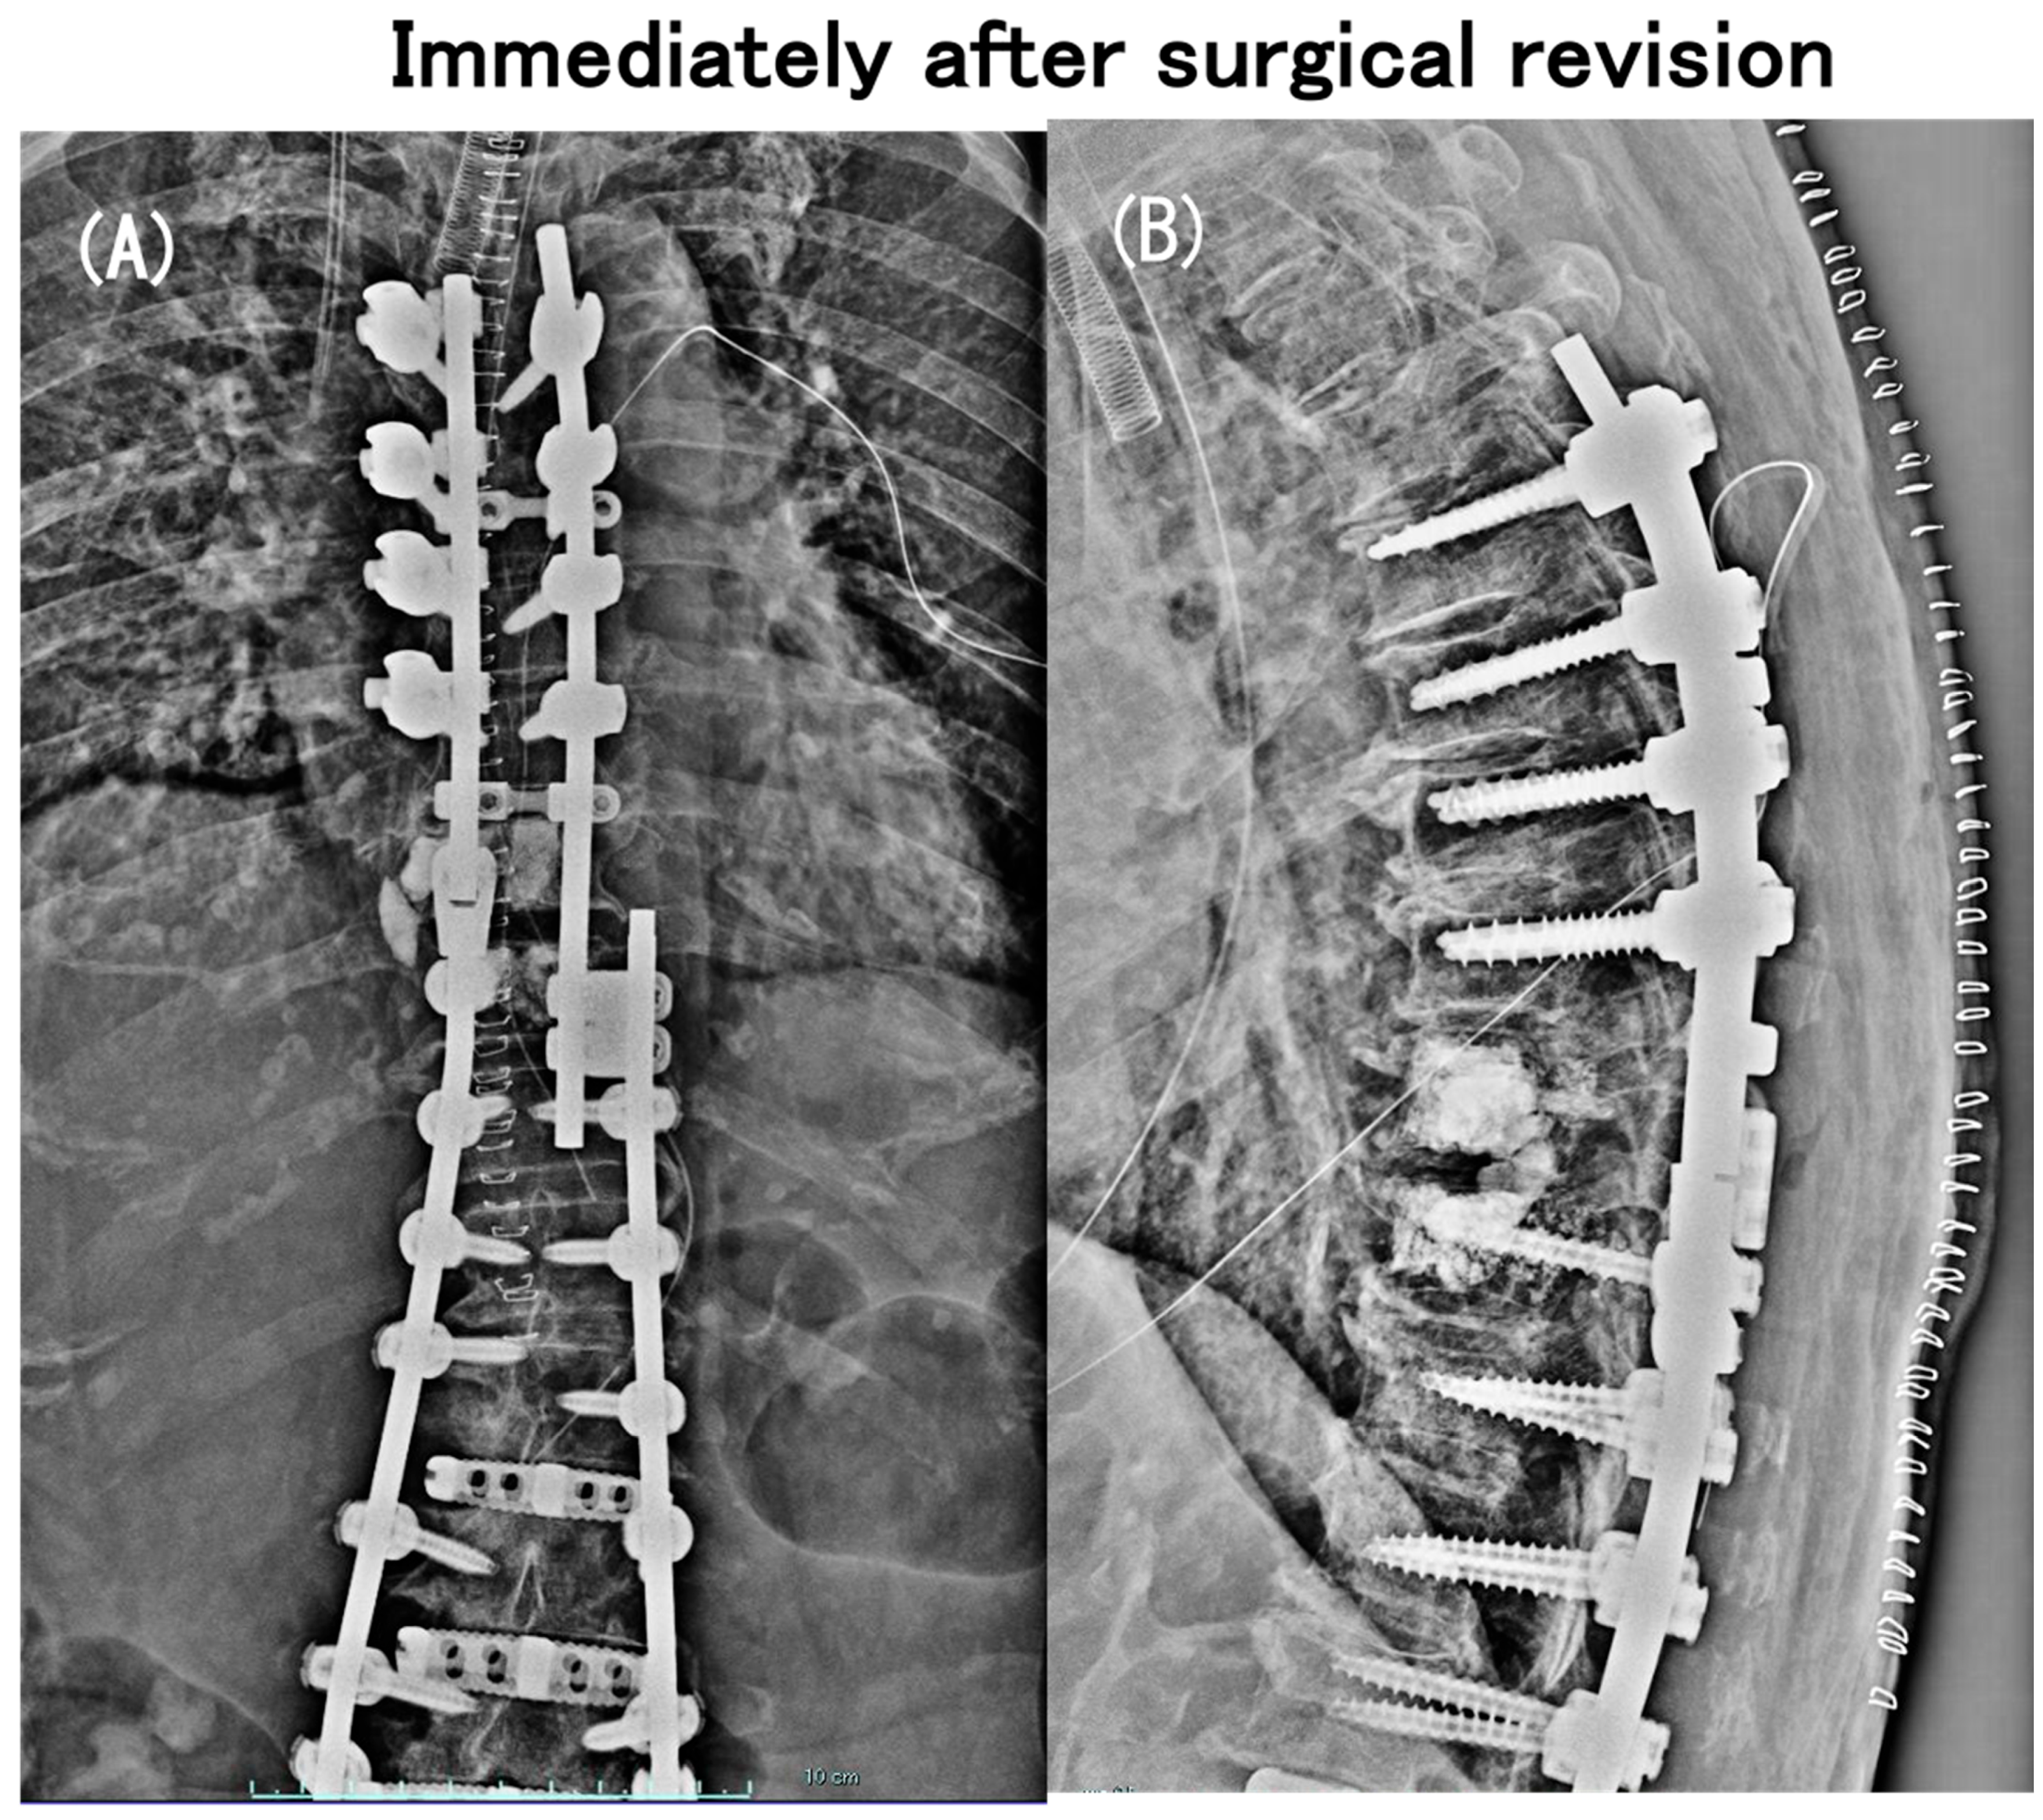

3.6. Case Presentation

- Case no. 6

- 2.

- Case no. 4